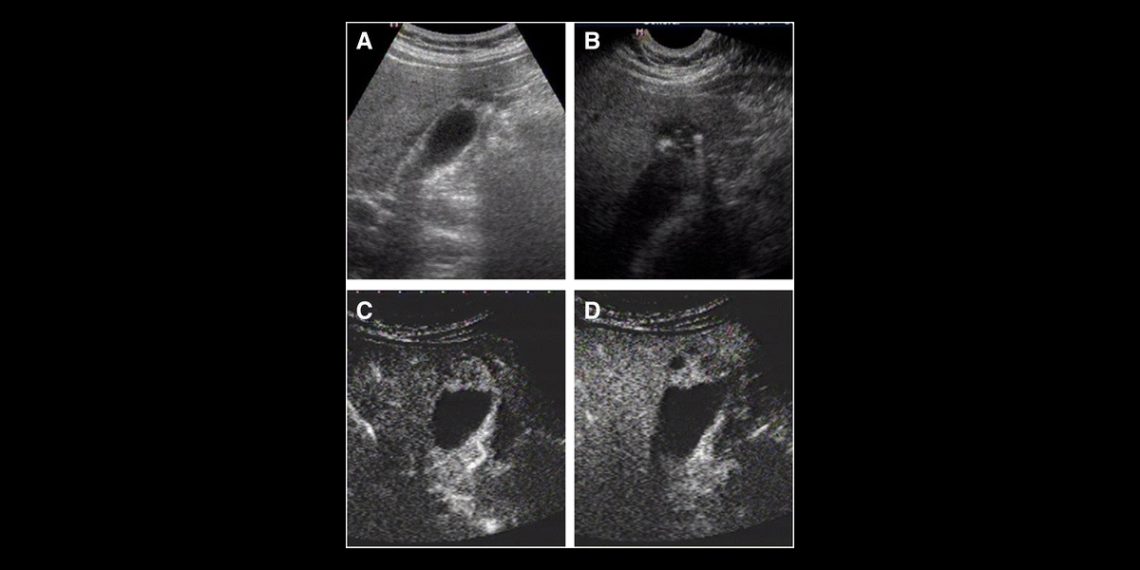

Diagnosis and Medical Imaging of Adenomyosis